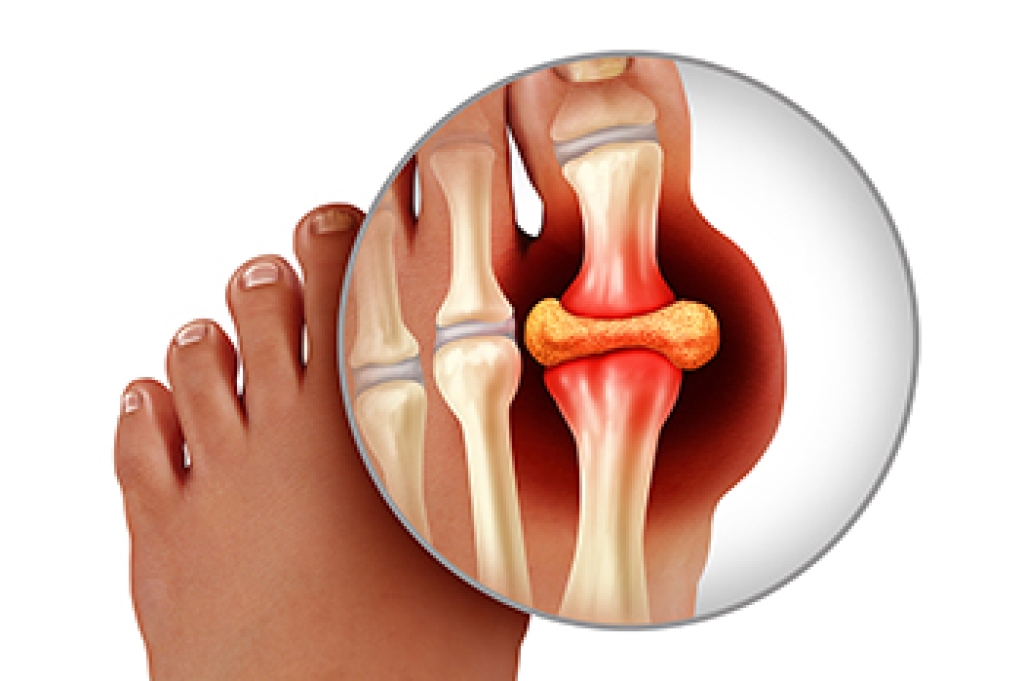

Arthritis is a joint disorder that involves the inflammation of different joints in your body, such as those in your feet. Arthritis is often caused by a degenerative joint disease and causes mild to severe pain in all affected areas. In addition to this, swelling and stiffness in the affected joints can also be a common symptom of arthritis.